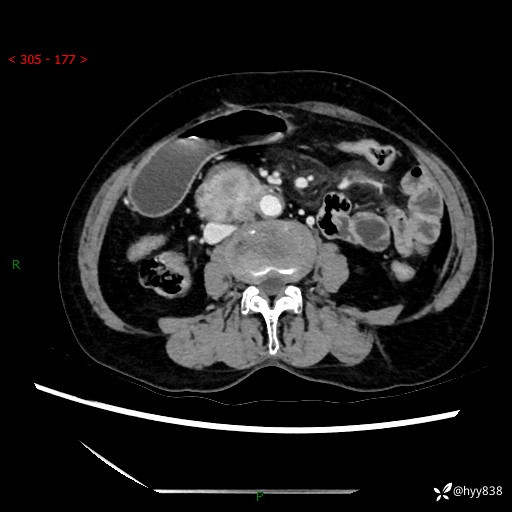

71岁/女,腹痛1月余。腹膜后肿物,间质瘤 VS 副节瘤 VS 平滑肌肉瘤---(有结果)

【患者信息】:71岁/女

【主诉】:腹痛1月余

【现病史及既往史】:患者于1月前无明显诱因出现右下腹部疼痛不适,呈阵发性隐痛,尚可耐受,放射至后背部及腰部疼痛,伴排便困难,不伴其它部位疼痛,无嗳气,无不洁饮食,无黑便,无恶心、呕吐、腹胀腹泻、呕血、发热、寒颤、厌油、黄疸,多次就诊于当地区太湖医院拍片示: 行抗炎等对症支持治疗,效果尚可。现患者上述不适症状明显进一步加重,为求进一步治疗遂来我院门诊就诊,门诊以“十二指肠肿瘤?”收住我科。 起病以来,精神、睡眠可,食欲可,大便异常、小便正常,体力、体重无明显下降。

【检查】:腹部CT增强扫描(外院CT平扫)